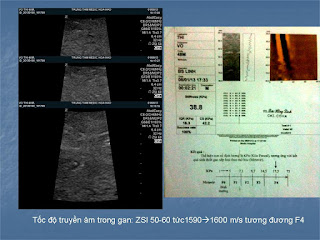

ĐO ĐỘ XƠ HÓA GAN BẰNG TỐC ĐỘ TRUYỀN ÂM

Phát hiện xơ hoá gan bằng cách đo tốc độ truyền âm